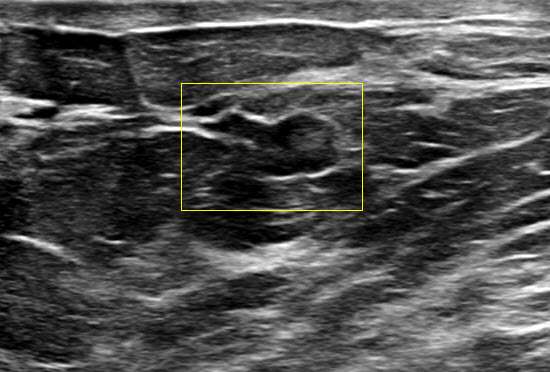

Ultrasound features include:

- Intraductal papillomas often appear as well defined solid intraductal masses within dilated ducts. They can exhibit a "frond-like" appearance projecting into the ductal lumen.

- Intraductal papillomas often demonstrate internal vascularity on color Doppler imaging. Furthermore, a vascular stalk may also be seen connecting to the ductal wall.